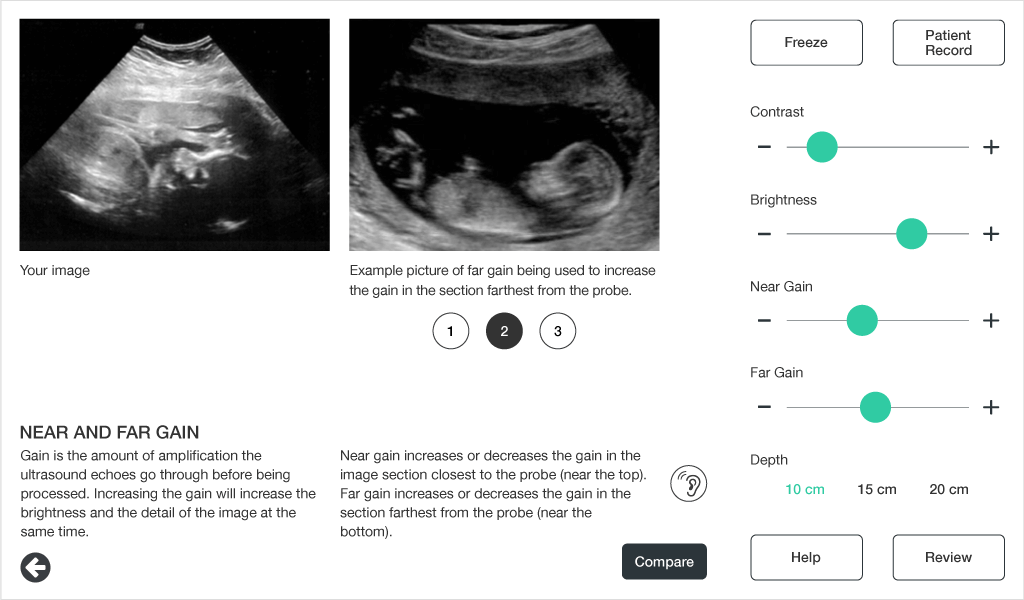

Comparing ultrasound images